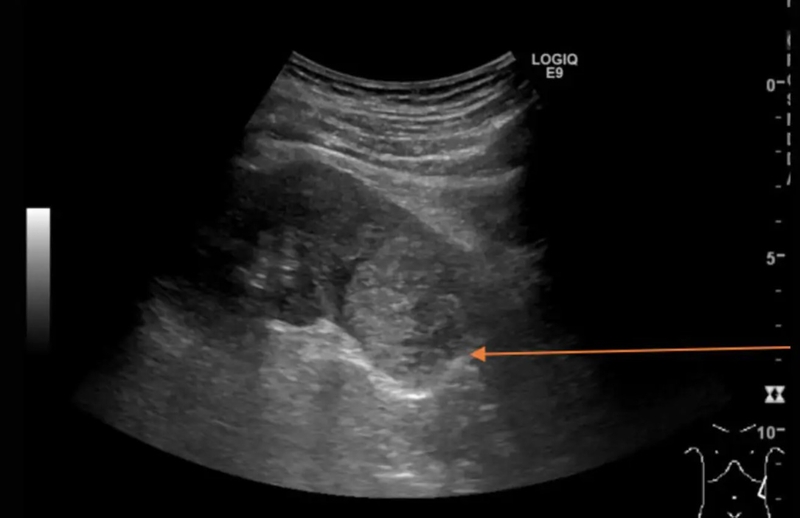

Siêu âm thận là kỹ thuật xét nghiệm không xâm lấn, sử dụng sóng âm để tạo ra hình ảnh về cấu trúc, kích thước bình thường của thận, cũng như đánh giá các dấu hiệu bệnh lý tại thận nếu có.

Xét nghiệm này giúp xác định vị trí, kích thước, cấu trúc, hình dạng và mối liên hệ giữa thận và các tạng khác. Đặc biệt hơn, siêu âm thận giúp chẩn đoán chính xác một số bệnh như sỏi thận, nang thận, áp xe thận và thận ứ nước.

Trên siêu âm thận, các bác sĩ sẽ quan sát và đánh giá được cấu trúc và kích thước bình thường của thận. Các đặc điểm của hai quả thận bình thường bao gồm: